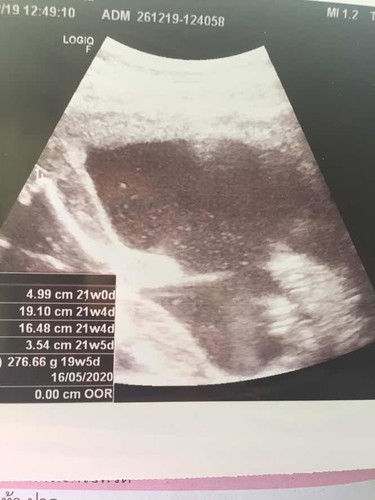

รุ้แค่ว่าน้องน้ำหนัก 276.66กรัม กำหนดคลอด ประมาน 16พ.ค.63 อายุครรภ์โดยประมาน 19วีค5วัน